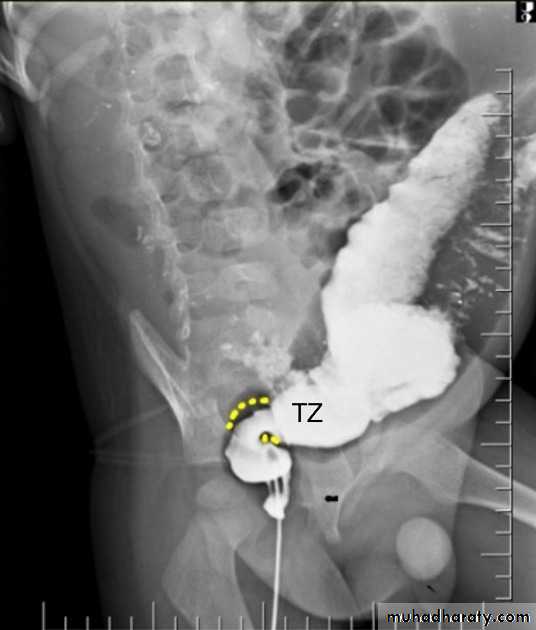

Hirschprung disease

is the most common cause of neonatal colonic obstruction (~15-20%). It is commonly characterized by a short segment of colonic aganglionosis affecting term neonates, especially boys.contrast enema

A carefully performed contrast enema is indispensable in both the diagnosis of Hirschprung disease but also in assessing the length of involvement. It should be noted however that the depicted transition zone on the contrast enema is not accurate at determining the transition between absent and present ganglion cells.

The affected segment is of small caliber with proximal dilatation Fasciculation/saw-tooth irregularity of the aganglion segment is frequently seen

Views of particular importance include:

early filling views that include rectum and sigmoid colon allowing for rectosigmoid ratio to be determined.

transition zone